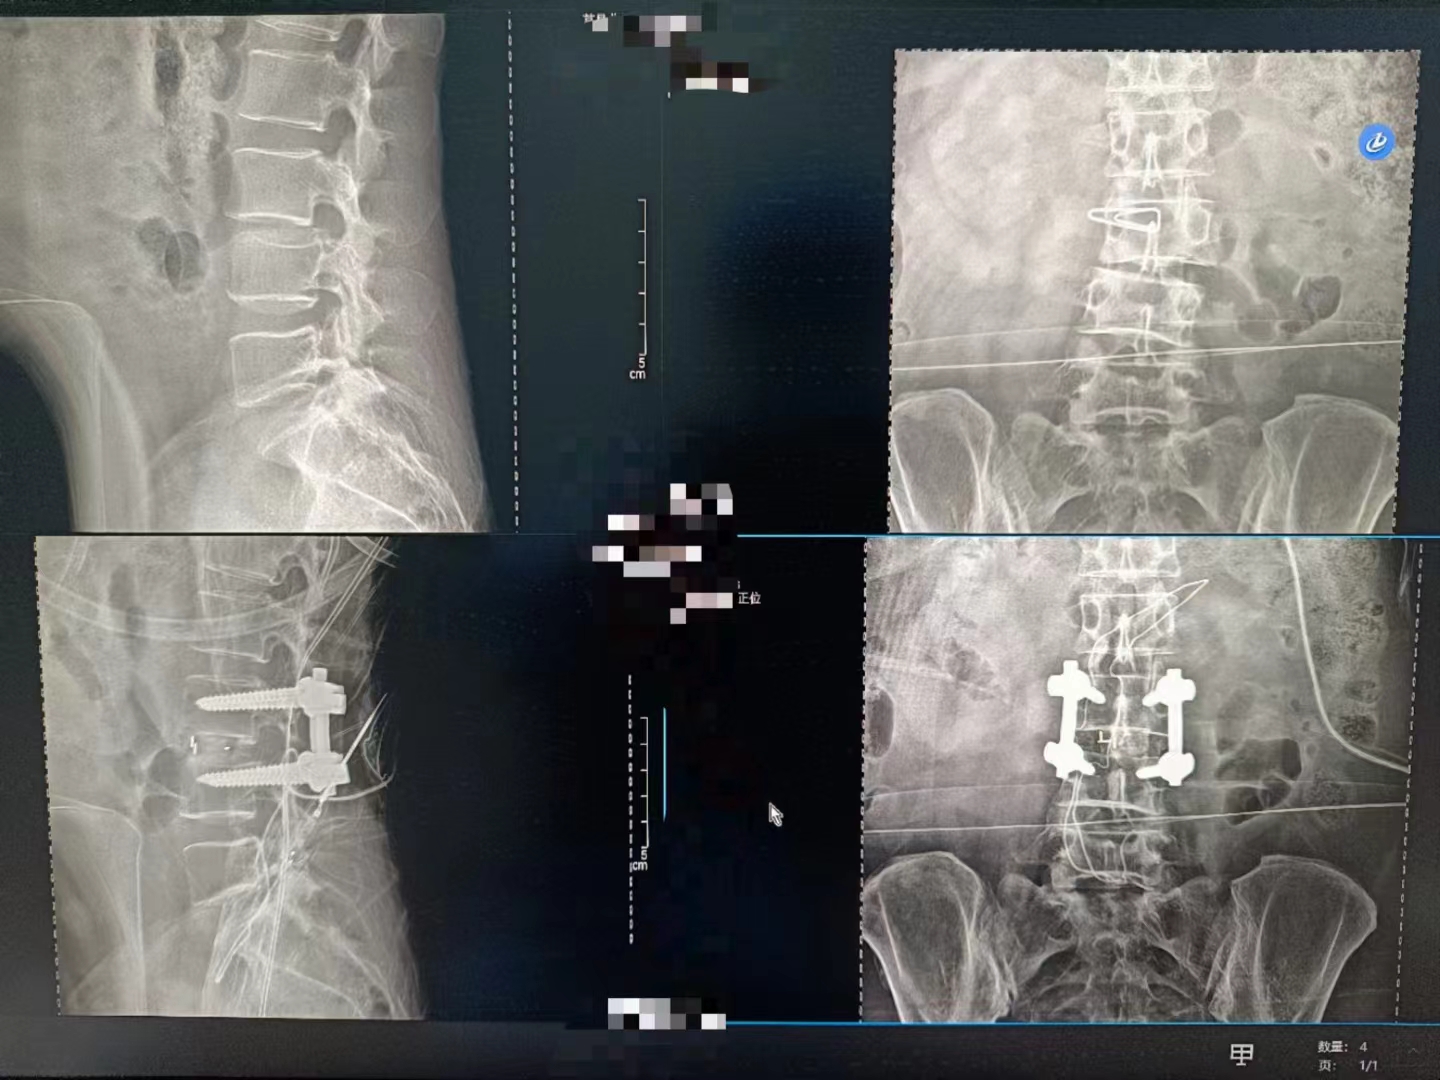

在今日晨曦的溫柔擁抱中,手術(shù)室里上演了一場(chǎng)科技與藝術(shù)的交融。一臺(tái)Dira-DRCF型數(shù)字化X射線攝影設(shè)備,宛如一位靜默的舞者,在手術(shù)醫(yī)生的嫻熟指揮下,翩翩起舞。

醫(yī)生們,身著綠衣,如同守護(hù)生命的使者,他們的雙手靈巧而堅(jiān)定,每一個(gè)細(xì)微的動(dòng)作都透露出對(duì)生命的敬畏與尊重。而這臺(tái)設(shè)備,則是他們手中的魔法棒,透過無形的射線,洞察生命的奧秘。

當(dāng)設(shè)備啟動(dòng),那束柔和的X射線穿過患者的身體,捕捉下每一個(gè)細(xì)微的影像。那一刻,時(shí)間仿佛凝固,所有的目光都聚焦在那塊屏幕上。那里,生命的紋理清晰可見,疾病的陰影無處遁形。

手術(shù)順利完成,當(dāng)醫(yī)生們露出疲憊而欣慰的笑容時(shí),我知道,那不僅僅是勝利的喜悅,更是對(duì)生命的敬畏與珍視。而這一切,都離不開這臺(tái)數(shù)字化X射線攝影設(shè)備的默默付出。